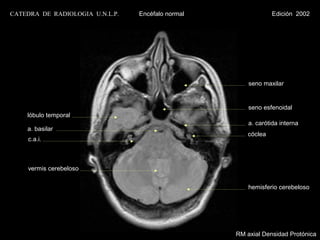

RM axial Densidad Protónica

CATEDRA DE RADIOLOGIA U.N.L.P.   Encéfalo normal                Edición 2002

seno maxilar

lóbulo temporal

a. carótida interna

bulbo

seno lateral

vermis cerebeloso

hemisferio cerebeloso

RM axial T1 con contraste

seno esfenoidal

a. basilar

cóclea

c.a.i.